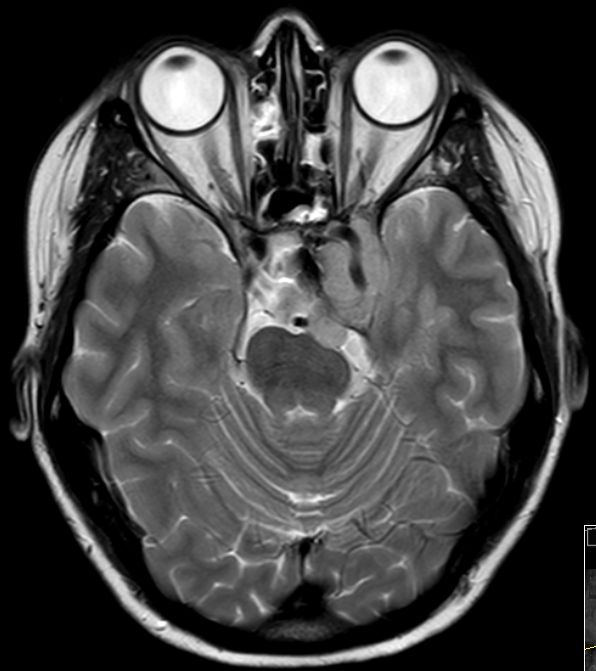

| Adenom | 42-jährige Krankenpflegerin mit

atypischem Hypophysenadenom. Z.n. transsphenoidaler Resektion. Hemianopsie

rechts. Großer extrasellärer Anteil. Ummauerung der Arteria carotis interna

links. Größe 4,2 x 4,2 x 2,7 cm überwiegend links der Mittellinie,

größenregredient, Ränder sind glatt begrenzt, die Kontrastmittelaufnahme

homogen. Ausdehnung vom Orbitatrichter in die Sella und nach dorsorostral bis

zum Hirnstamm und die Temporalgrube.![]() | ||||